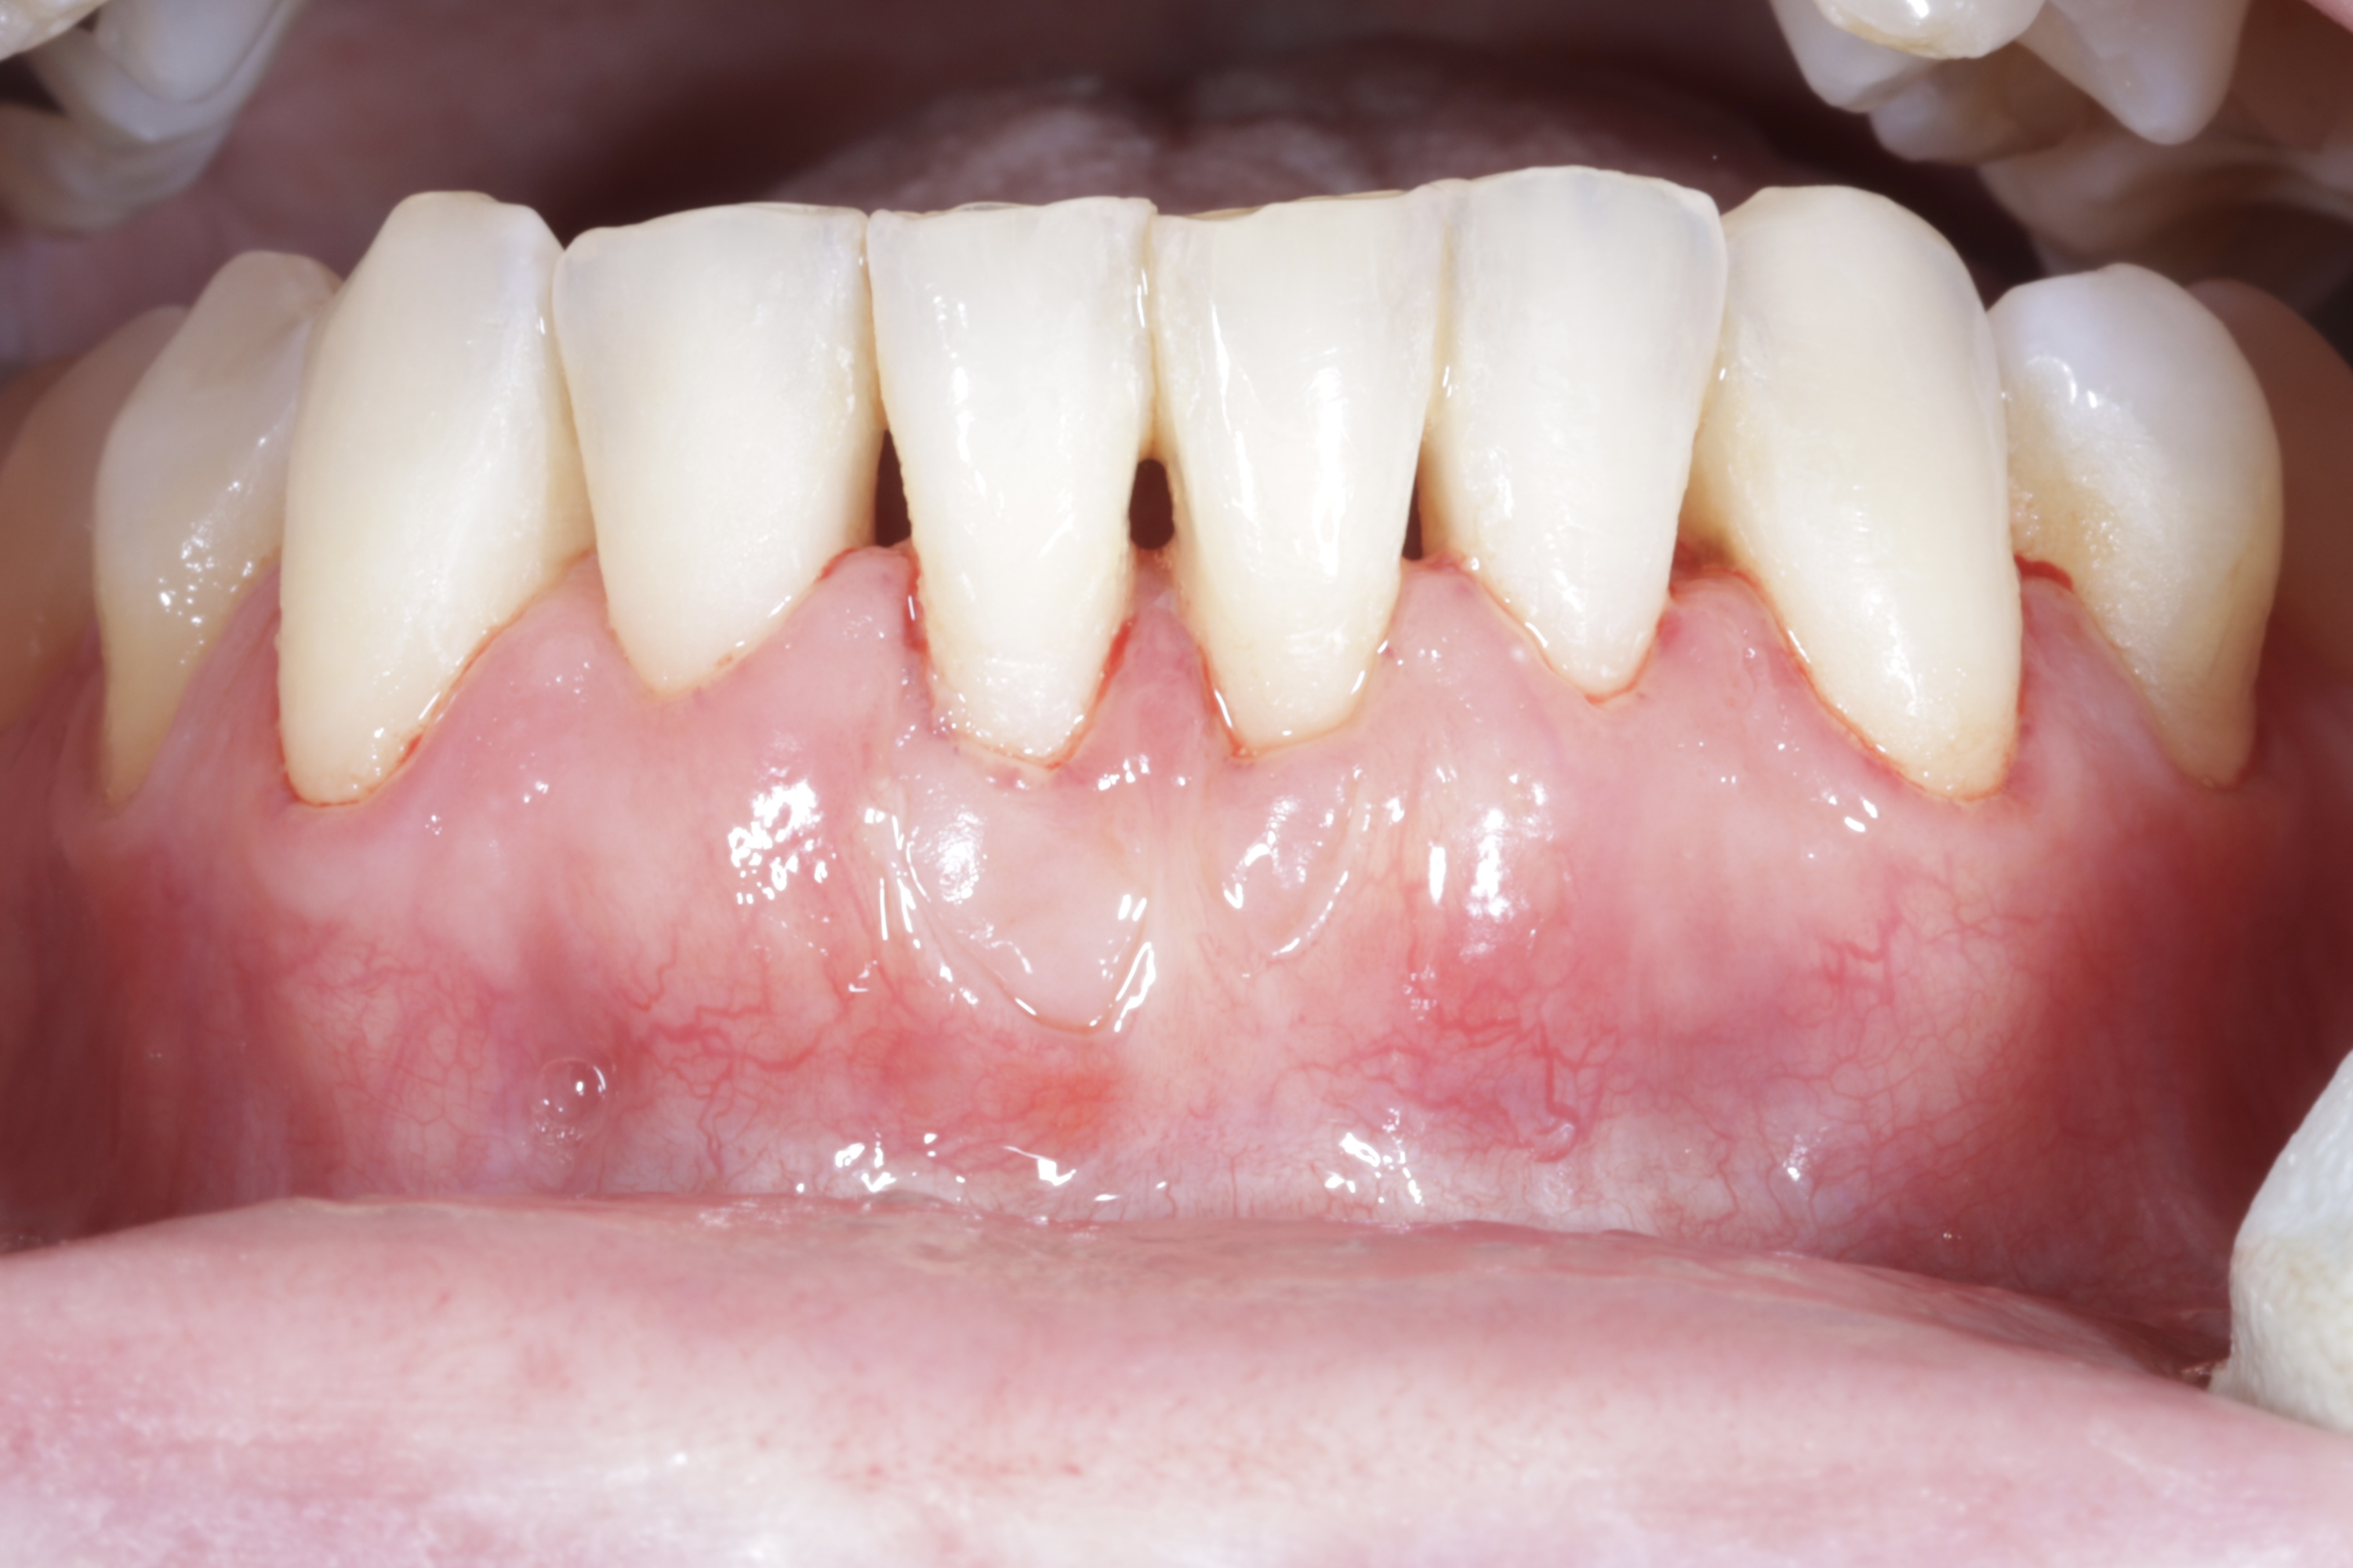

Estarás de acuerdo en que los tejidos duros alrededor de dientes e implantes son muy importantes, pero...

... ¿sabías que los tejidos blandos son los que garantizan la estabilidad ósea?

¡Sí, como estás leyendo! La ausencia de una suficiente cantidad y calidad, es decir, de grosor y ancho